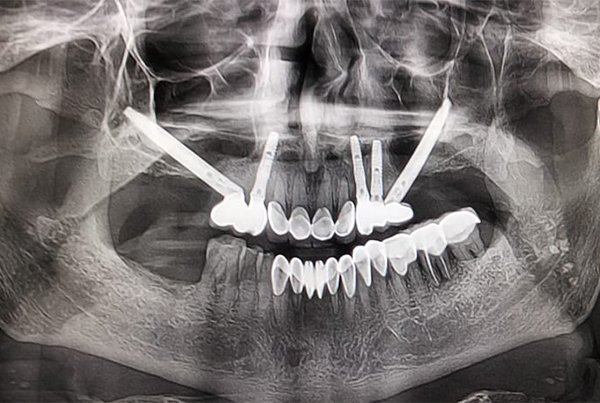

Zygomatic Implants

Advanced implant solution for patients with severe upper jaw bone loss.